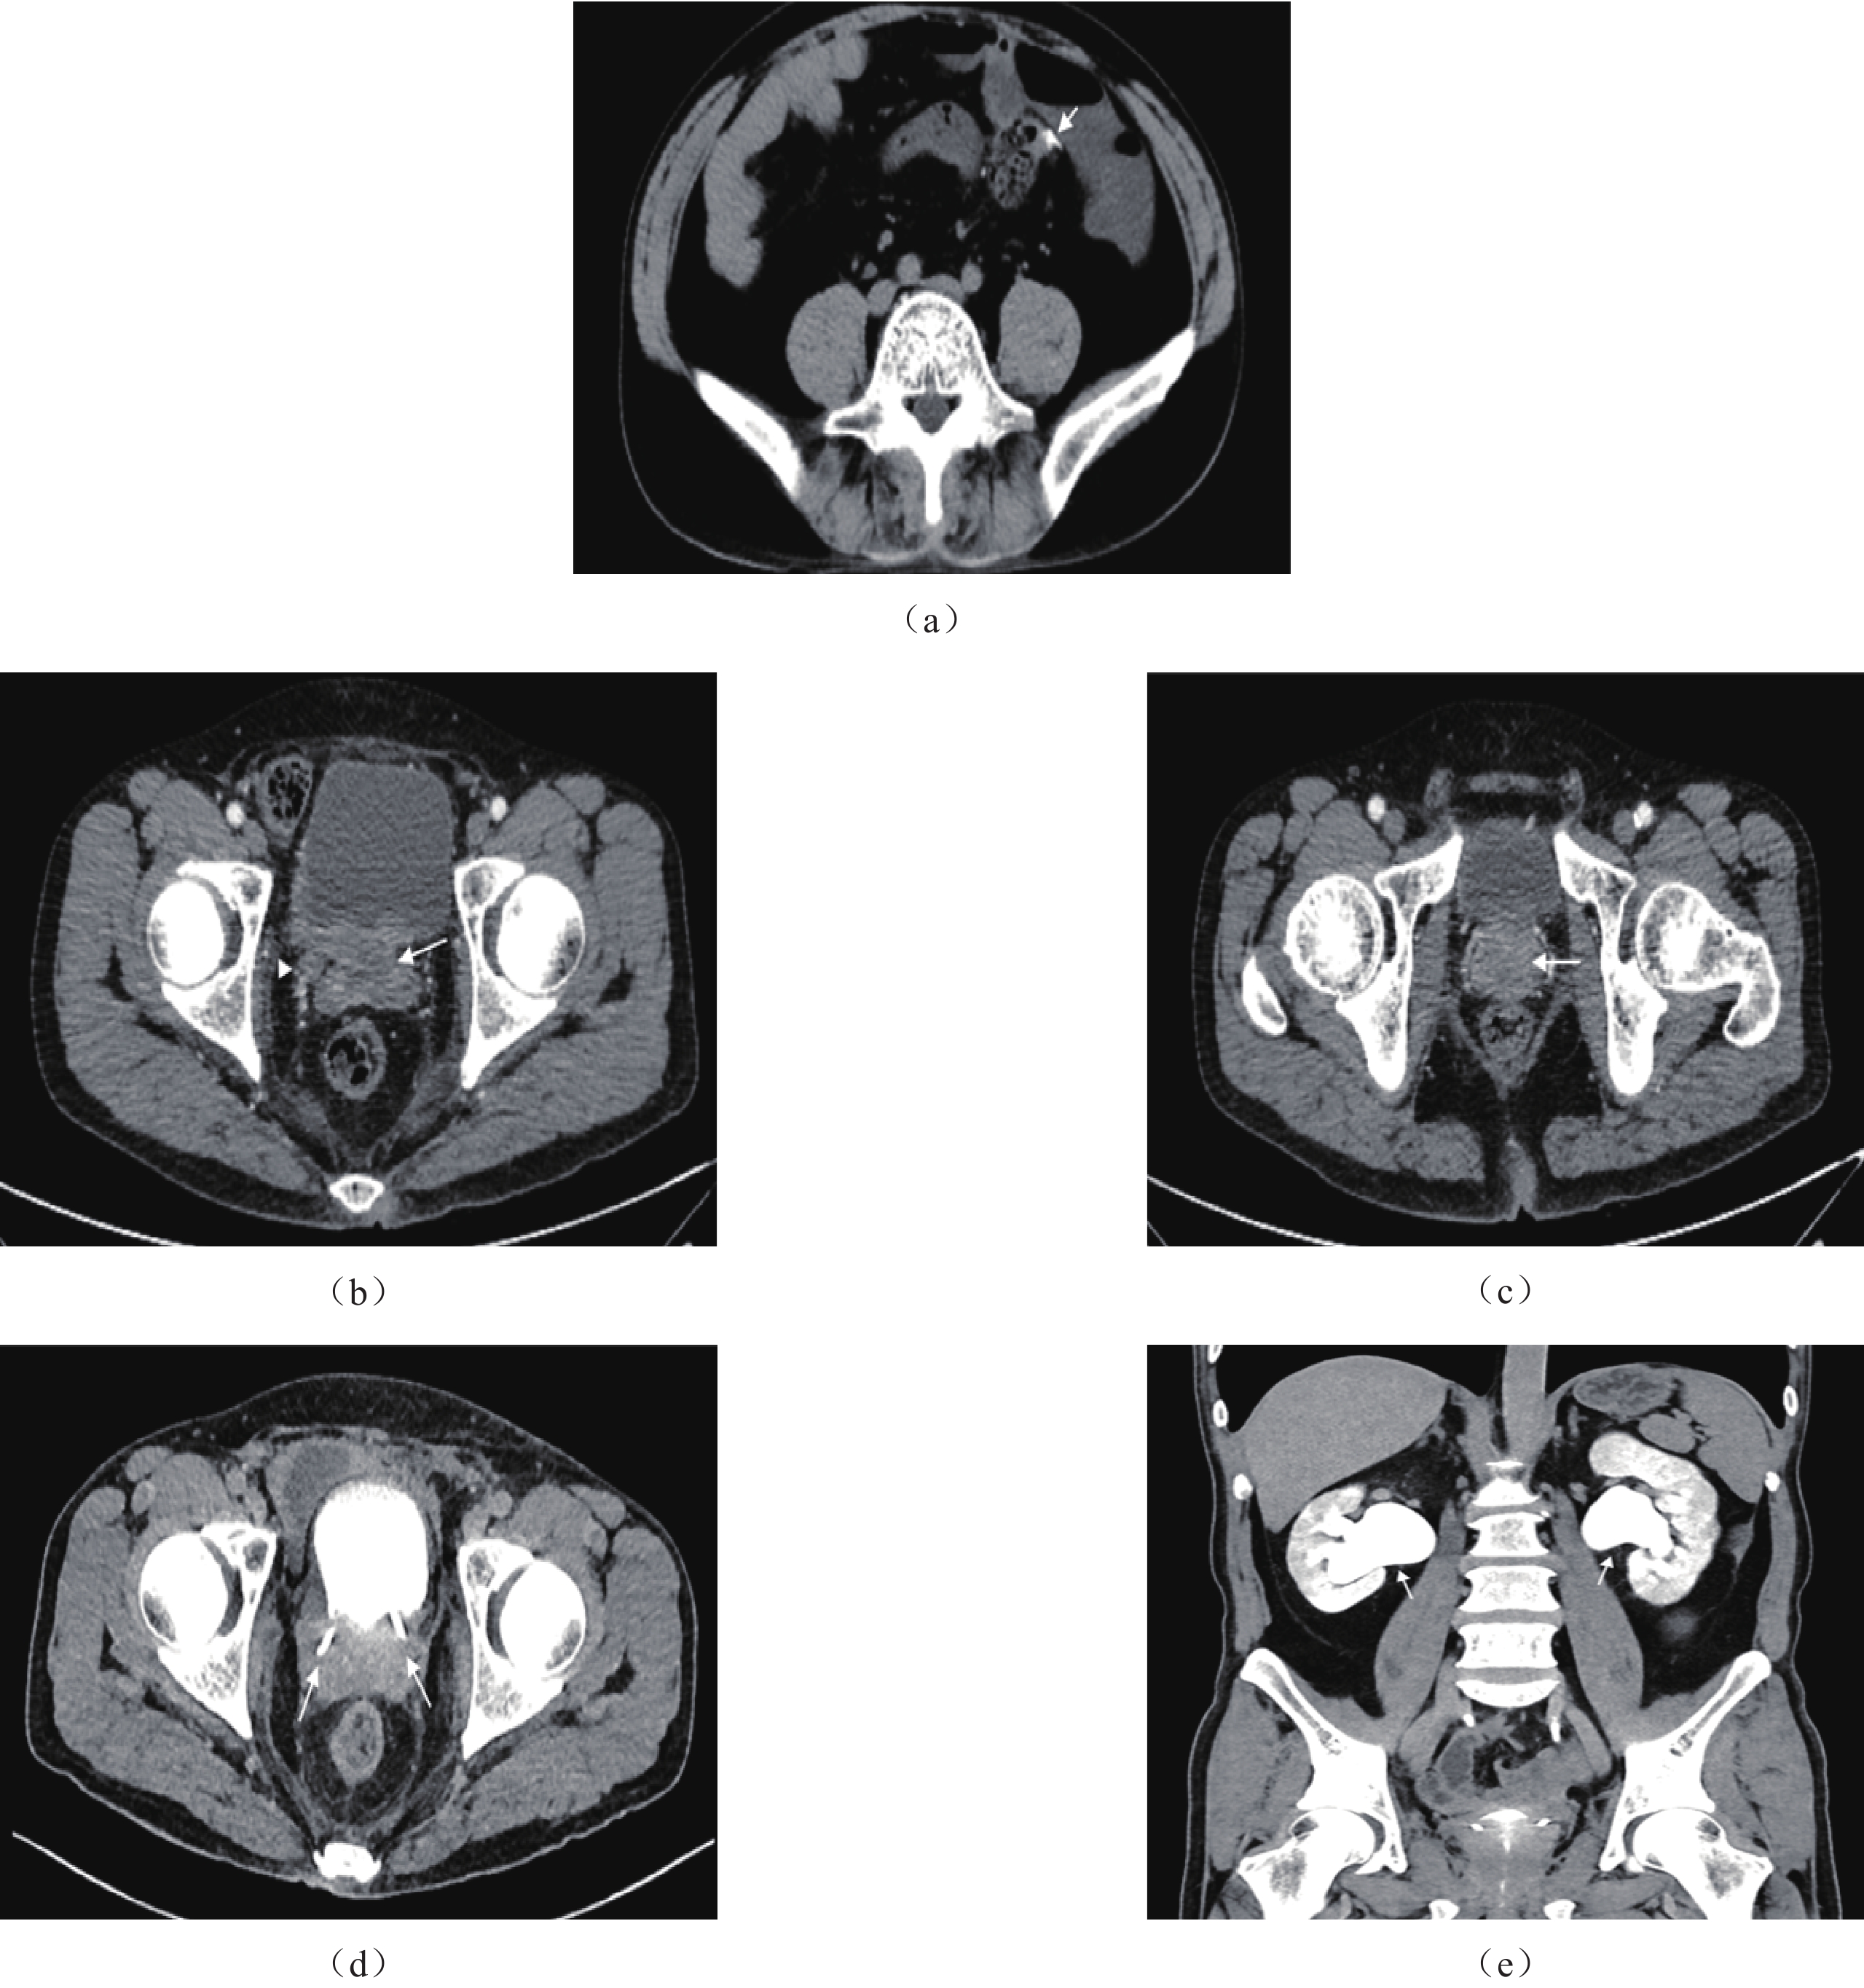

CT表现。①膀胱后壁−前列腺−两侧精囊区占位,双侧输尿管下段受累。②肿块形态不规则,边界欠清。③增强扫描不均匀强化。④双侧尿路积水扩张,膀胱周围局部脂肪间隙模糊,盆腔内多发淋巴结影(图1)。

鉴于其罕见性,只有少数病例报告描述了前列腺SCC的影像学表现;其表现为非特异性,包括前列腺肿大伴有增强的分叶状软组织肿块、局部侵袭和远处转移[19]。此外,患者往往表现出由晚期疾病引起的梗阻性尿路病变症状。

CT检查可显示广泛的骨转移及腹部和盆腔淋巴结肿大[20]。MRI上,肿瘤通常较大且异质性明显,在T1WI上呈现低到中等信号强度,在T2WI上信号强度较高,并在高b值DWI上显示高信号,而在ADC成像上则呈现中等低信号强度。这些肿瘤在使用钆增强时显著增强[21]。

本例患者CT及MRI可显示肿瘤累及膀胱后壁和双侧精囊腺,增强扫描可见肿瘤不均匀强化。CTU有助于显示双侧尿路积水,MRI的多序列成像则更清楚显示肿瘤侵及的范围并有助于良恶性的判断。